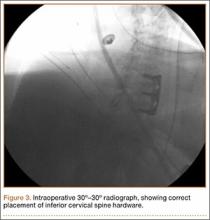

A 54-year-old man with a body mass index (BMI) of 50 presented with neck and bilateral arm pain, with left greater than right radicular symptoms in the C6 and C7 distribution. Magnetic resonance imaging (MRI) showed disc herniations at C5-C6 and C6-C7 with spinal cord signal changes, and he underwent a C5-C6 and C6-C7 anterior cervical discectomy and fusion. Initial localization was determined using a lateral radiograph and vertebral needle. During hardware placement, anteroposterior and lateral fluoroscopic radiographs confirmed adequate placement of the superior screw, but visualization of the inferior portion of the plate and inferior screw was challenging (Figure 2). Our oblique 30º–30º view provided better visualization of the plate and screws in the lower cervical vertebrae than lateral imaging, and allowed confirmation that the hardware was positioned correctly (Figure 3). It took 1 attempt to achieve adequate visualization with the 30º–30º view.